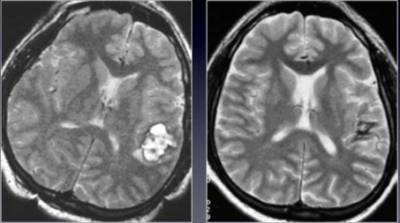

Врачи отмечают, что гемангиома головного мозга у взрослых является редким, но важным заболеванием, требующим внимательного подхода. Это доброкачественная опухоль, состоящая из кровеносных сосудов, которая может проявляться различными симптомами, включая головные боли, судороги и неврологические нарушения. Специалисты подчеркивают, что диагностика гемангиомы часто осуществляется с помощью МРТ, что позволяет точно определить ее размер и расположение. Лечение может варьироваться от наблюдения до хирургического вмешательства, в зависимости от клинической картины и состояния пациента. Врачи рекомендуют не игнорировать симптомы и обращаться за медицинской помощью при их появлении, так как ранняя диагностика и правильное лечение могут значительно улучшить качество жизни.

- Неинвазивные – магнитно-резонансная томография и компьютерная томография помогают получать объемное изображение, с помощью которого создается полноценный вид исследуемого органа.

КТ

Компьютерная томография менее информативна при диагностике головного мозга, уступая МРТ в точности и объективности выдаваемых данных. В некоторых случаях может использоваться контраст, с помощью которого будут заметны даже самые маленькие опухоли.